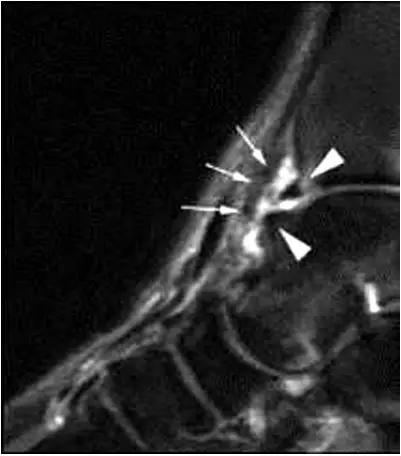

2、影像学表现:

- 踝关节正侧位X 线平片,侧位片均显示距骨后方有三角形或椭圆形的距后三角骨。部分病例伴有轻度的踝关节骨性关节病。

- MRI 检查示距后三角骨及周围软组织有水肿信号,距后三角骨和距骨之间正常的低信号纤维连接中断,出现液性信号。

3、MR表现:

- 三角籽骨或距骨后三角结构模糊和变形,T1WI信号降低, T2WI信号升高,

- 周围脂肪水肿,

- 踇趾长屈肌腱信号升高,见鞘膜积液,

- 胫骨后下跟骨上缘骨结构形态变化和信号异常,

- 三角籽骨和距骨退行性囊变。

三角籽骨综合征

三角籽骨综合征并跟腱滑囊积液